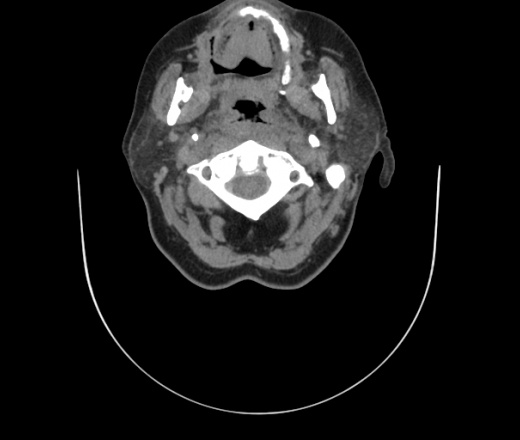

Женщина поступила в х/о спустя 4 дня после того как при употреблении карася подавилась костью.

Наличие газа в средостении на протяжении тел С2-С6 (медиастинальна эмфизема); рыбная кость на уровне тела С6.

При всем уважении, но говорить о медиастинальной эмфиземе, оценивая мягкие ткани шеи, как-то слишком резко. На мой взгляд, это ретрофарингеальное пространство.

Эвакуировали почти 100мл гноя. Но кость не смогли найти. Думаю что она даст дальнейшее ослоднение. Эндоскопически за черпалонадгортаной звязкой не смогли зайти в пищевод, все мягкие ткани отечные, просвет пищевода сдавлен. По всей видимости параэзофагеальная клетчака тоже задействована. Эмпиема, если ее можно так назвать, незнаю как правильно дошла до уровня яремной вырезки. Чем закончиться напишу. Ждем медиастинита.

Флегмона заглоточного пространства шеи, только операция, флегмоны вскрывают. Риск медиастинита.

Согласен с Вами; конечно, наличие газа в клетчатке ретрофарингеального пространства (затмение с опечаткой..). К сожалению, процесс "продвигается" к медиастиниту. Но почему никто, не отмечает наличие рыб. кости; или это для Всех очевидно?

Кость то мы сразу выявили, размеры где то 17*2мм, но ее так и не получается найти в этой каше